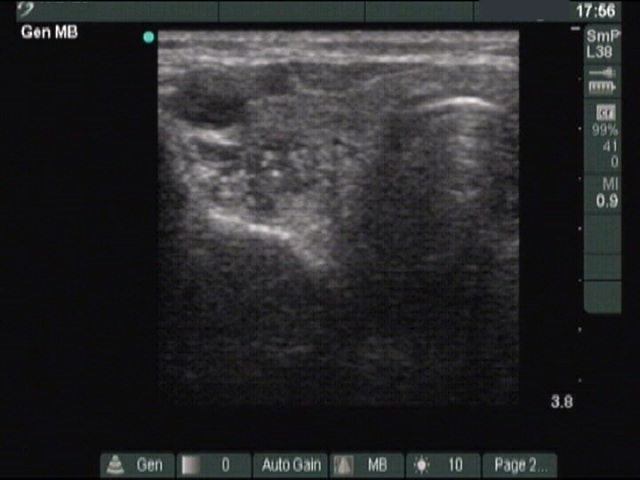

Ultrasonography: There were three hypoechogenic lesions wich has hyperechogenic granules larger than foci of microcalcification. There was a lymph node above the left lobe. The node lacked a regular hilum and was round

Comment. The coarse and large hyperechogenic figures seen on ultrasonography correspond to amyloid deposits. In contrast with coarse calcification, there is no acoustic shadow dorsal to amyloid. The foci of amyloid are much larger than a microcalcification. The specificity of this type of hyperechogenic figures is around 50%.